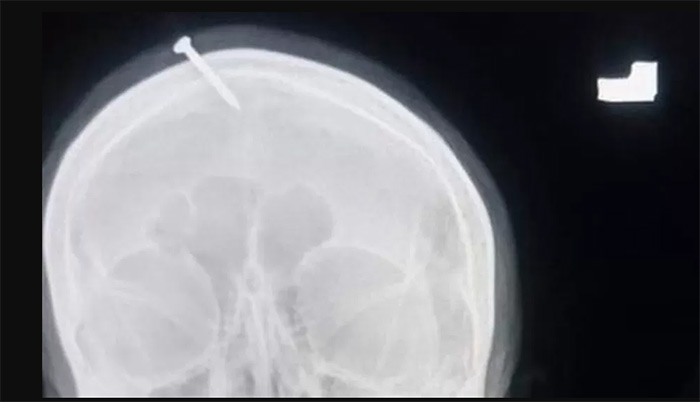

เหตุการณ์ดังกล่าวเกิดขึ้นเมื่อเดือนกุมภาพันธ์ 2565 โดยจากรายงานของสำนักข่าวบีบีซี เผยว่า ตำรวจปากีสถานได้ออกล่าตัวเพื่อจับกุมหมอผีรายที่ทำพิธีตอกตะปูใส่กะโหลกศีรษะของหญิงตั้งครรภ์ หลังจากมีภาพเอกซเรย์ชวนสะพรึงของเธอถูกแชร์ไปว่อนโลกออนไลน์

รายงานเผยว่า หญิงตั้งครรภ์ที่ไม่เผยชื่อรายนี้ มาขอความช่วยเหลือจากแพทย์ที่โรงพยาบาล Lady Reading Hospital ในเมืองเปศวาร์ หลังจากที่เธอพยายามใช้คีมคีบตะปูยาว 5 เซนติเมตร ออกจากศีรษะของตัวเอง แต่ไม่สำเร็จ โดยตอนแรกเธออ้างว่าเป็นคนตอกตะปูใส่ศีรษะตัวเอง จนต่อมาจึงยอมรับว่าเป็นฝีมือของหมอฝี ที่ยืนยันว่าการทำเช่นนี้จะช่วยให้เธอคลอดลูกออกมาเป็นเด็กชาย

ภาพจาก LADY READING HOSPITAL

ดร.ไฮเดอร์ ข่าน แพทย์ผู้ทำการรักษา เผยว่า หญิงรายนี้ยังมีสติรู้ตัวดีตอนมาถึงโรงพยาบาล แต่อยู่ในสภาพที่เจ็บปวดอย่างมาก

สำหรับเคสนี้ พบว่าทางแพทย์ช่วยนำตะปูออกจากศีรษะของหญิงตั้งครรภ์ได้สำเร็จ ขณะที่ทางหัวหน้าตำรวจเมืองเปศวาร์ได้จัดตั้งชุดสอบสวนพิเศษตามล่าตัวหมอผีดังกล่าวมารับโทษ หลังล้อเล่นกับชีวิตของคนบริสุทธิ์ด้วยคำสัญญาจอมปลอม พร้อมกันนั้นจะมีการสอบสวนเจ้าหน้าที่ของโรงพยาบาลด้วย ที่ไม่แจ้งเรื่องต่อทางตำรวจตั้งแต่ตอนที่หญิงรายนี้เข้ามาที่โรงพยาบาล